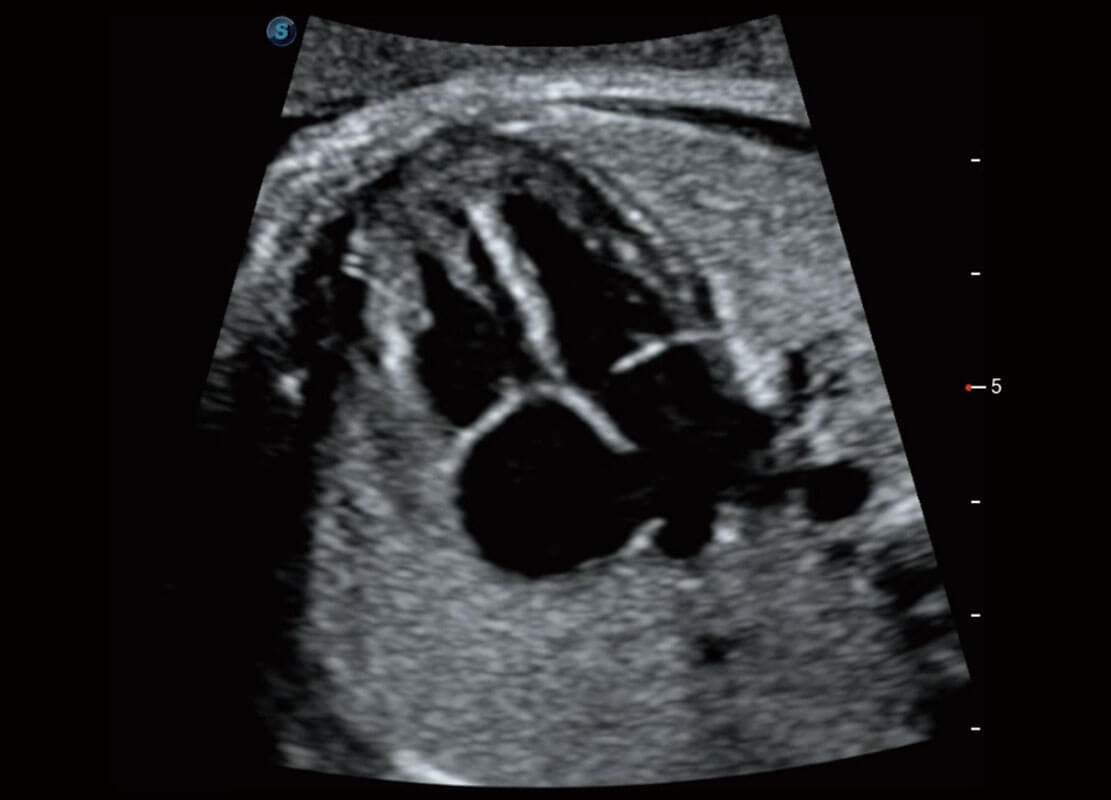

腔内妇科-宫腔分离

腔内妇科-卵巢

P60优异的图像质量搭载专科探头,在妇科基础疾病的诊断、卵泡生长的监测、输卵管通畅情况的判别等方面为您提供生殖应用方案。